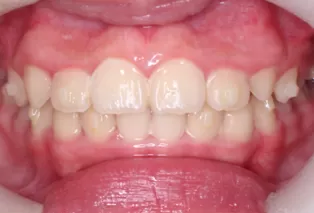

Intraoral photos after treatment